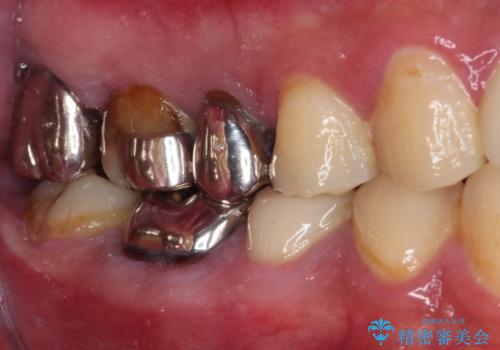

- ものが挟まるとのことで来院された患者様です。

一度は治療せずに放置していましたが、1年後のメインテナンスの際に悪化していることが分かったことから、補綴治療を行うこととしました。

神経を抜いてある歯はむし歯が進行しても痛みを感じることがないため、気がついたときには著しくむし歯が進行している可能性があります。

早めの対応とすることで、抜歯を回避できることはもちろん、外科処置などの本来必要のない処置を行わずに対処することができました。